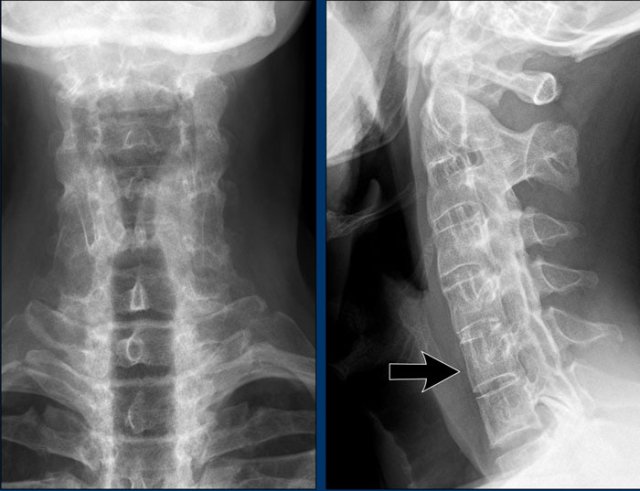

Atlanto-axial subluxation due to rheumatoid arthritis of the cervical spine Atlanto-axial subluxation due to rheumatoid arthritis of the cervical spine

Atlanto-axial subluxation

The cervical spine is often affected in rheumatoid arthritis and can present as atlantoaxial instability, subaxial subluxation or basilar invagination with cranial settling.

Cranial settling occurs when the dens extends into the foramen magnum.

Atlanto-axial subluxation is an important and potentially life threatening complication of rheumatoid arthritis. It is defined when the space between the dens of C2 and the arch of the atlas exceeds more than 3 mm. It is caused by inflammatory ligamentous laxity.

Instability in this joint may result in numerous neurological symptoms due to compression of the spinal cord.

Images

In flexion of the cervical spine there is widening of the distance (14 mm) between the dens and the posterior surface of the anterior atlas ring (normal ≤3 mm).